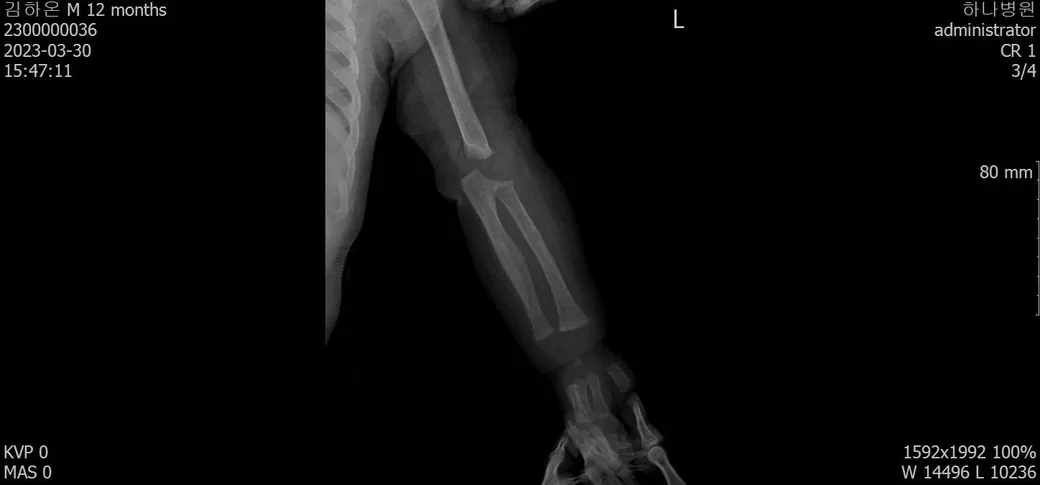

다름이 아니라, 첨부드린 엑스레이(X-ray) 사진처럼 골절 사실을 알게 되고 골절 발생 시점 대략적으로나마 추정시기를 파악하려고 문의 드리게 되었습니다

1) 3월 30일 촬영한 X-ray만으로 정확한 골절 시기를 100% 특정하는 데에는 한계가 있다는 점 충분히 인지하고 있기에 촬영날짜 기준으로 대략적으로 어느정도 시점에서 발생되었을 것으로 추측(ex 당일, 7~10일전, 7~14일 전, 10일 ~ 20일전, 14일 ~ 30일전 등등등)되는지 이해하고 싶습니다.

• 3번 째 사진

보호자분이 원하시는 것은 2023-03-30에 골절이 된 사진만 가지고 언제 골절이 되었는지 추정을 하고 싶다는 말씀이죠? 3번째 사진에서 주변살들이 많이 부어있거나 하지 않아서 시간이 어느 정도 지난 것으로 보이네요. 초기유합은 1-2개월 정도 걸리는 것으로 알려져 있는 것으로 알려져 있으니 그 정도를 생각할 수 있을 것 같네요. 추정일 뿐입니다.